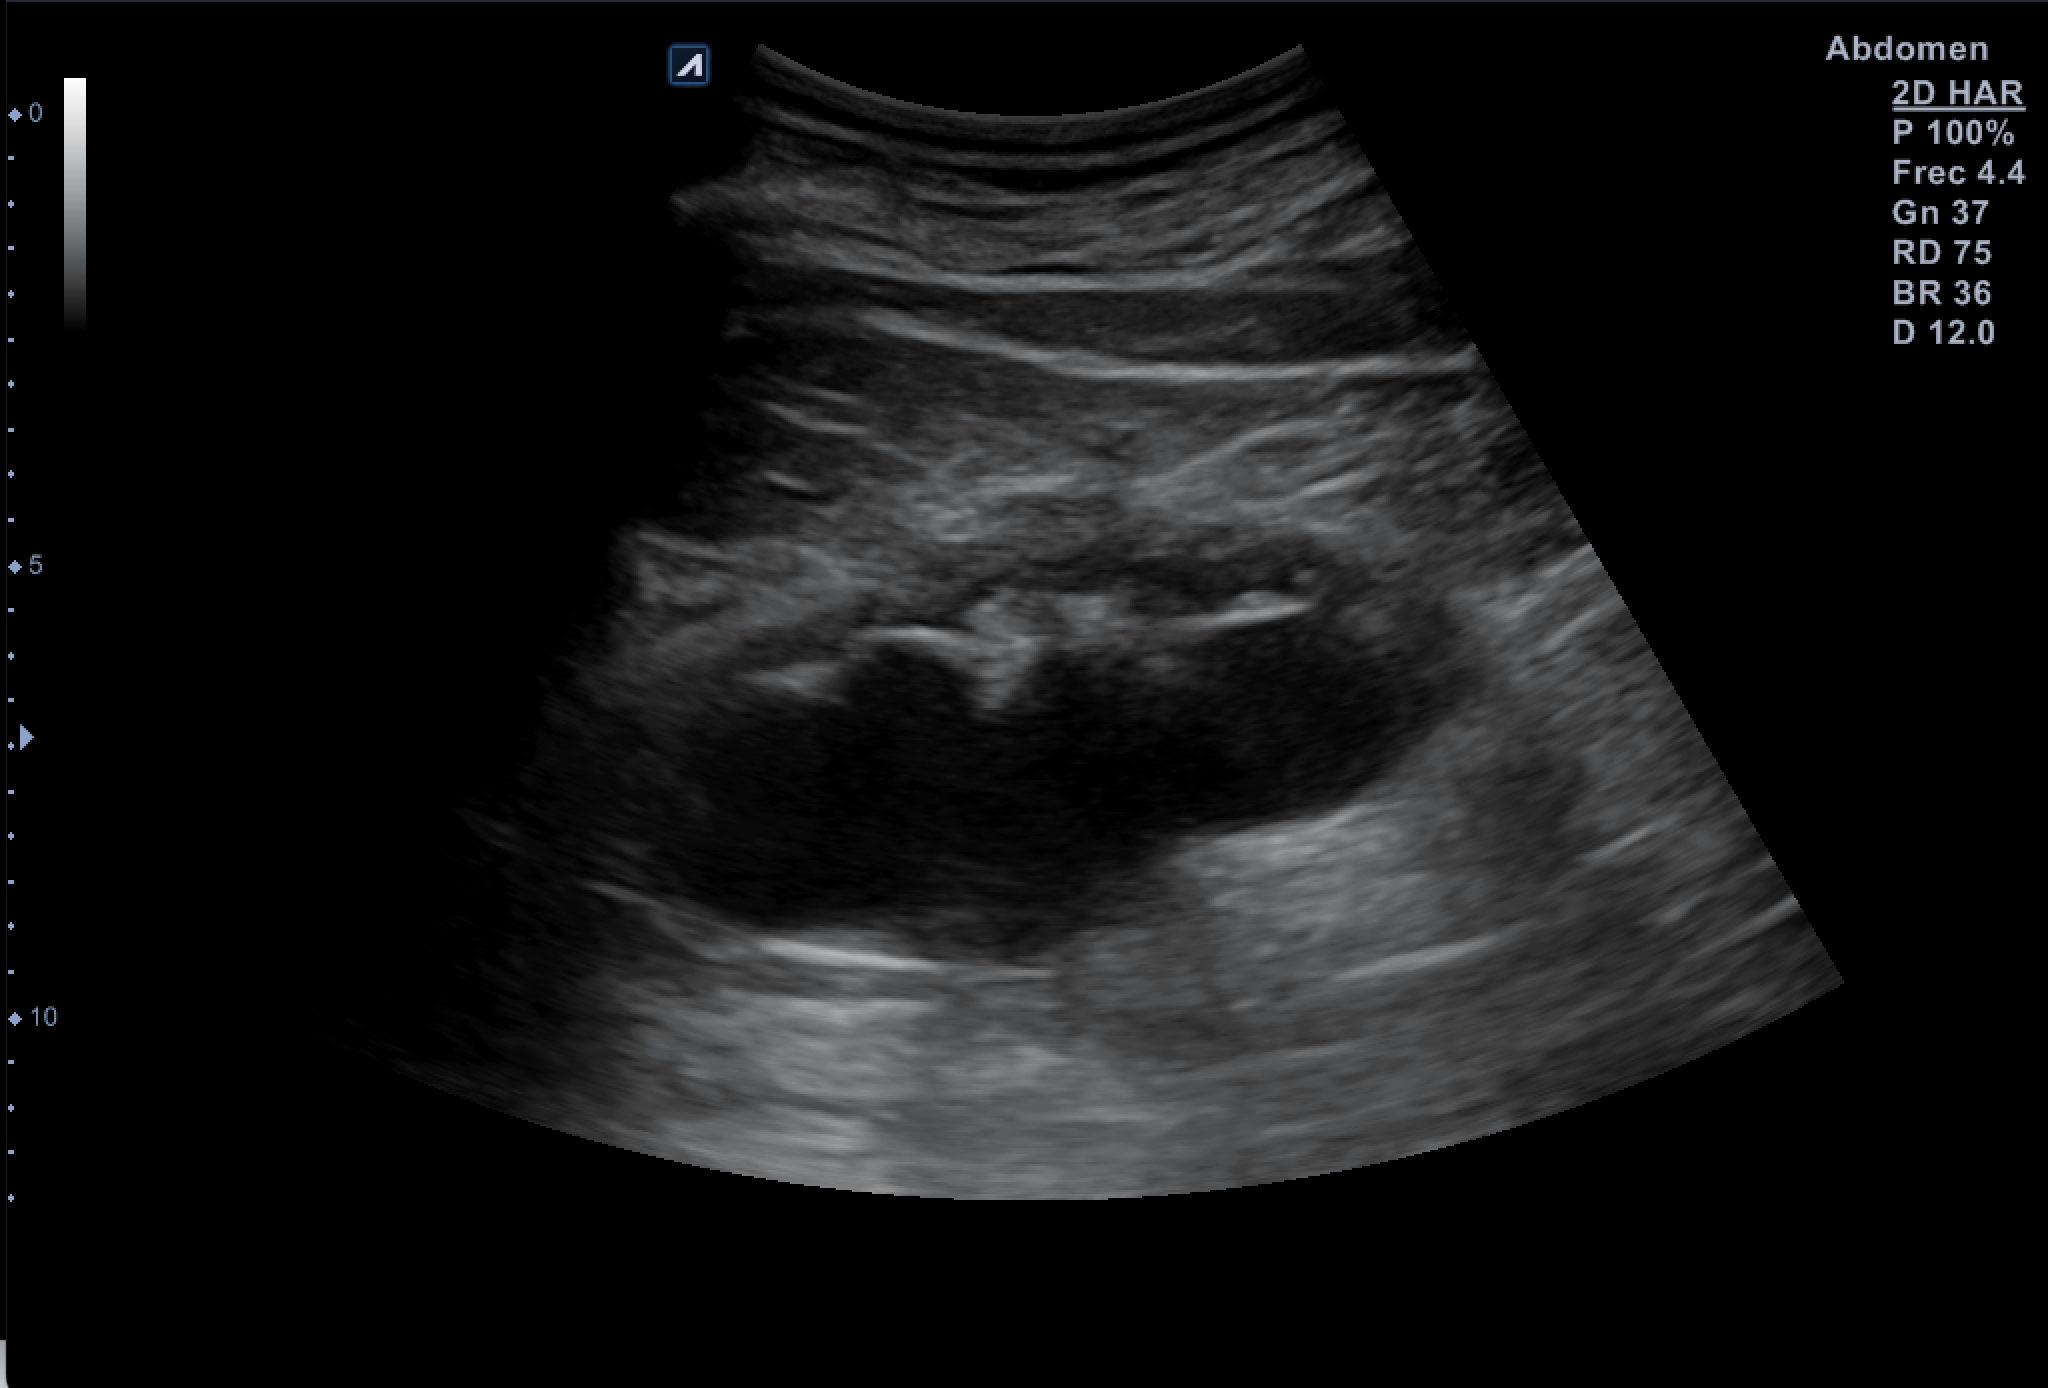

Hallazgos ecográficos

Tras valoración vesicoprostática con vejiga normal, jet vesicales visibles con próstata de 45 cc y residuo postmiccional mínimo. Riñón derecho como normal de tamaño y morfología sin dilataciones pielocaliciales (11 cm de tamaño). El Riñón Izquierdo (RI: 9 cm) presentaba una hidronefrosis grado IV y atrofia cortical con pelvis renal distendida, no consiguiendo detectar la causa obstructiva y considerando la posibilidad de una estenosis de la unión pieloureteral y como segunda opción una litiasis  ureteral pese a la normalidad de los jets vesicales.

Hidronefrosis del Riñón Izquierdo secundaria a estenosos de la unión pieloureteral por rama arterial.